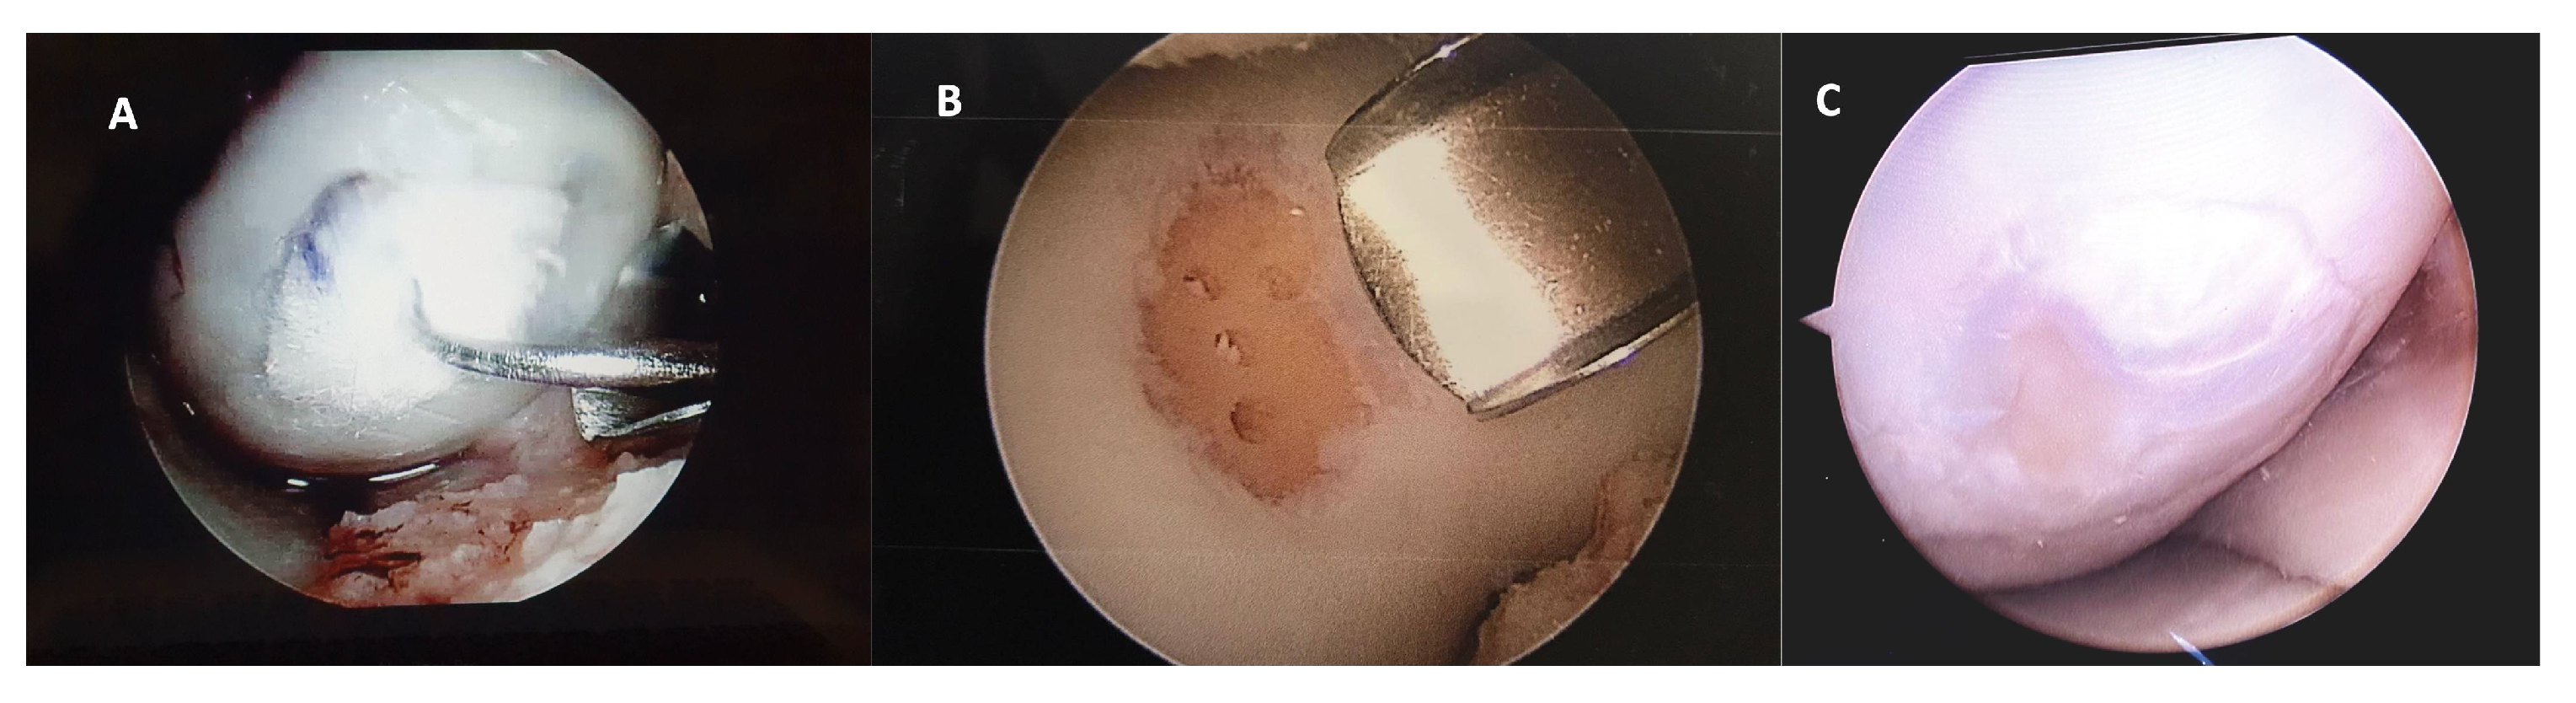

After 12 months of follow-up, a small number of patients required a new second-look arthroscopy, during which the integrity of the graft was verified to assess the degree of defect, fill, graft integration to the adjacent normal articular surface, and gross appearance of the graft surface. We were unable to observe a case without integration into adjacent normal articular tissue (Figure 4).

Figure 4.

Representative macroscopic view of the cartilaginous repair tissue within the circular full-thickness cartilage defects and adjacent cartilage during surgery for (A) the HA 3-D scaffold and (B) the microfractures groups. Letter (C) is the macroscopic view of the second-look arthroscopy (after 12 months) for the patient treated with HA 3-D scaffold with the graft completely integrated to the normal adjacent articular surface, without evident filling defects.